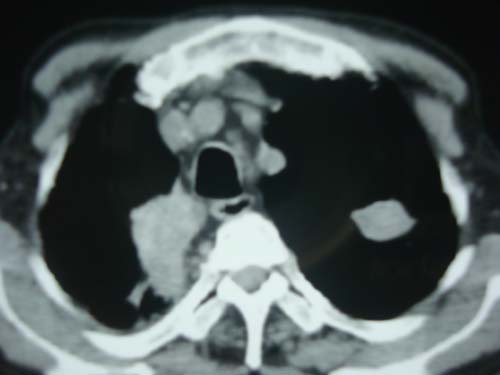

男性,45岁,胸疼,低热,抗炎治疗后症状缓解拍片检查发现左上肺有高密度灶,考虑结核,做ct示条件有限采集了部分图像,图像质量差请谅解

病灶有分叶 毛刺 左侧叶裂上移 考虑肺癌可能性大 建议穿刺

右上肺结核,左上肺周围型肺癌可能性大

考虑两肺上叶继发性肺结核;肺气肿(多发肺大泡)。

问下职业史,矽肺结节也说不定。